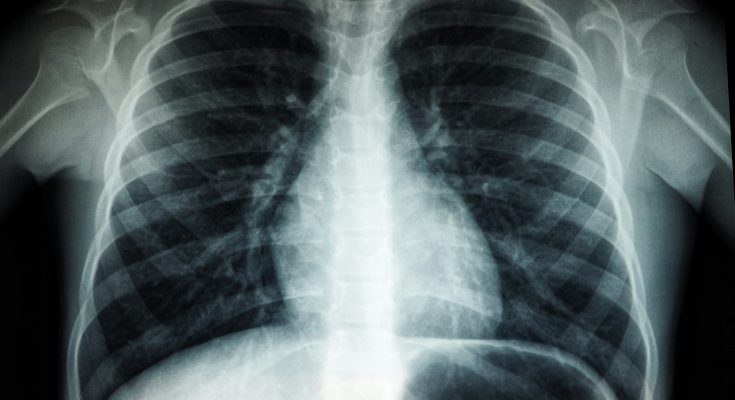

TB is caused by bacteria that most often affects the lungs. Every day, over 3,300 people die from the disease, with Southeast Asia accounting for nearly 40 per cent of deaths. Yet it is both preventable and treatable, including by using the antibiotic rifampicin.